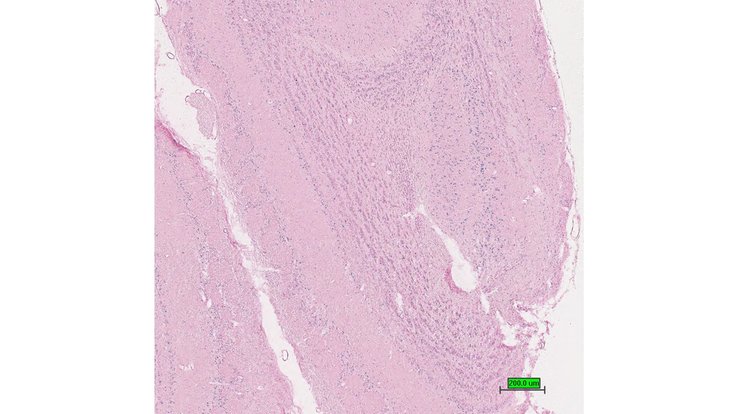

TS28: trachea Present UC Davis_1885937

Specimen UC Davis_1885938: postnatal adult; Ubxn2atm1b(EUCOMM)Hmgu/Ubxn2a+ (more )

Structure Level Pattern Image Note

TS28: trachea Present UC Davis_1885938

TS28: trachea Present UC Davis_1885990

Specimen UC Davis_1885991: postnatal adult; Ubxn2atm1b(EUCOMM)Hmgu/Ubxn2a+ (more )

TS28: esophagus Present UC Davis_1885991